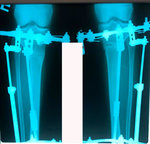

Дата операции - 24.10.2019г.

Дата снятия аппаратов - 22.01.2020

Срок сращения - 89 дней.